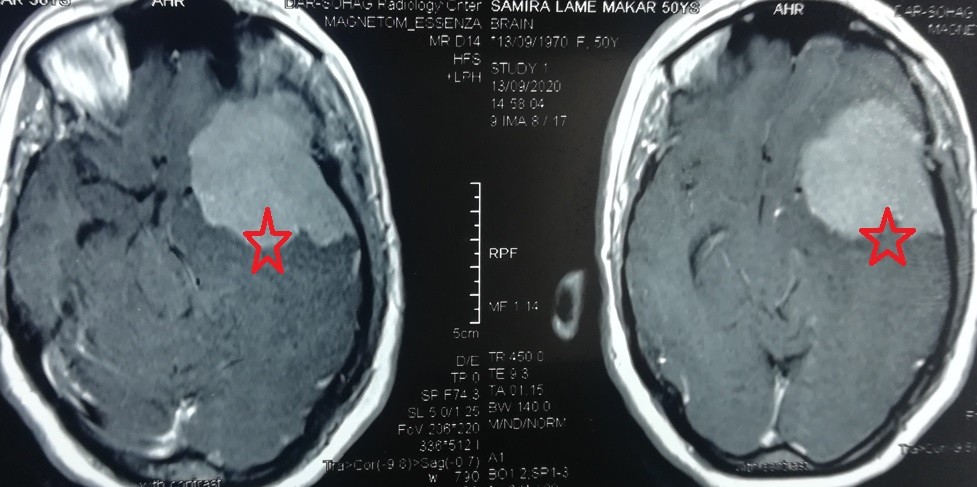

massive meningioma at the base of the skull on the left side of the temporal lobe